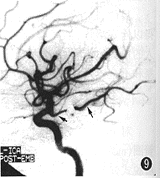

图6~9 基底动脉顶端动脉瘤过度栓塞。

图6~8为右椎动脉造影前后位像:图6为栓塞前;图7为栓塞后即刻造影,见动脉瘤完全栓塞,左侧大脑后动脉显影良好(短箭头),但弹簧圈少许凸入左大脑后动脉起始部(长箭头);图8为数分钟后再次造影,见左大脑后动脉几乎闭塞(箭头)。图9为栓塞后左颈内动脉造影侧位像,见左大脑后动脉(长箭头)经左后交通动脉(短箭头)显影良好

图6~9所示基底动脉顶端动脉瘤(图6),栓塞后即刻经椎动脉造影见动脉瘤100%栓塞,弹簧圈少许凸入左大脑后动脉起始部,但左侧大脑后动脉通畅(图7),数分钟后再次造影发现左大脑后动脉几乎完全闭塞(图8),所幸的是经左颈内动脉造影见左大脑后动脉经左后交通动脉显影良好(图9)。而发生过度栓塞的大脑中动脉瘤,栓塞前脑血管造影未见明显血管痉挛,动脉瘤栓塞时的最后1个GDC弹簧圈送入后即刻造影显示载瘤动脉通畅无损,但弹簧圈解脱后约10 min再造影见载瘤动脉血流明显变慢,虽经扩容、抗凝和扩张血管等治疗,病人最终因同侧大脑半球大面积脑梗死而死亡。可见术中及时准确地识别过度栓塞十分重要。